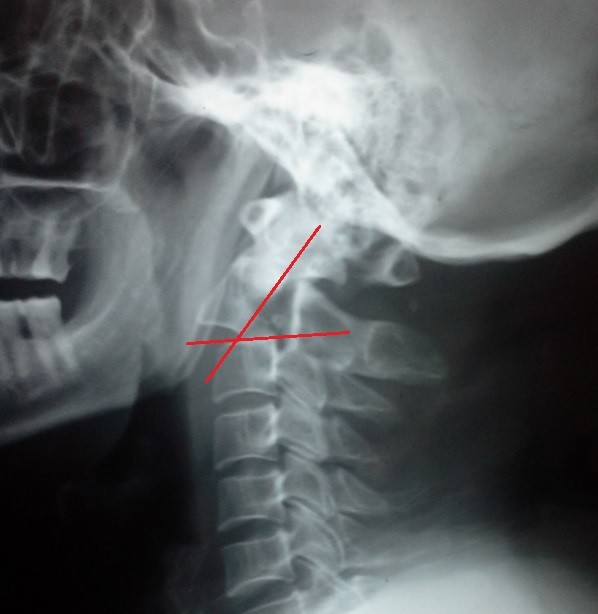

fracture of the second cervical vertebra with displacement between the second and third cervical